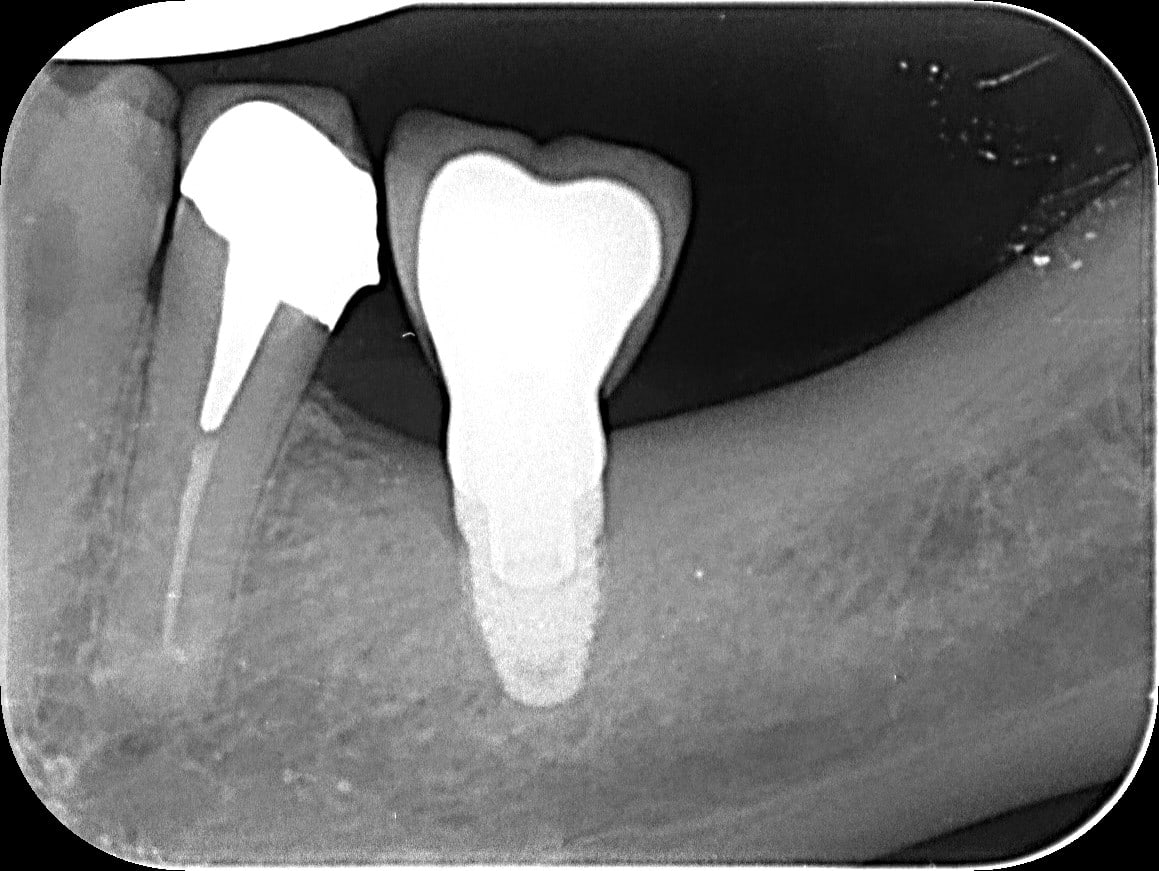

Je cherche à identifier cet implant posé en 2012-2013, probablement en région parisienne.

de très grandes chances que çà soit un Nobel replace trilobe vue la connexion....